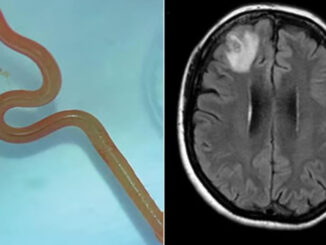

Descoberta: Verme com 8 cm é encontrado em cérebro humano: “Está vivo e se mexe”

29 de agosto de 2023 Redação 0

Uma mulher de 64 anos, natural de Nova Gales do Sul, foi internada hospital de Canberra, na Austrália, onde deu entrada na unidade com queixas […]